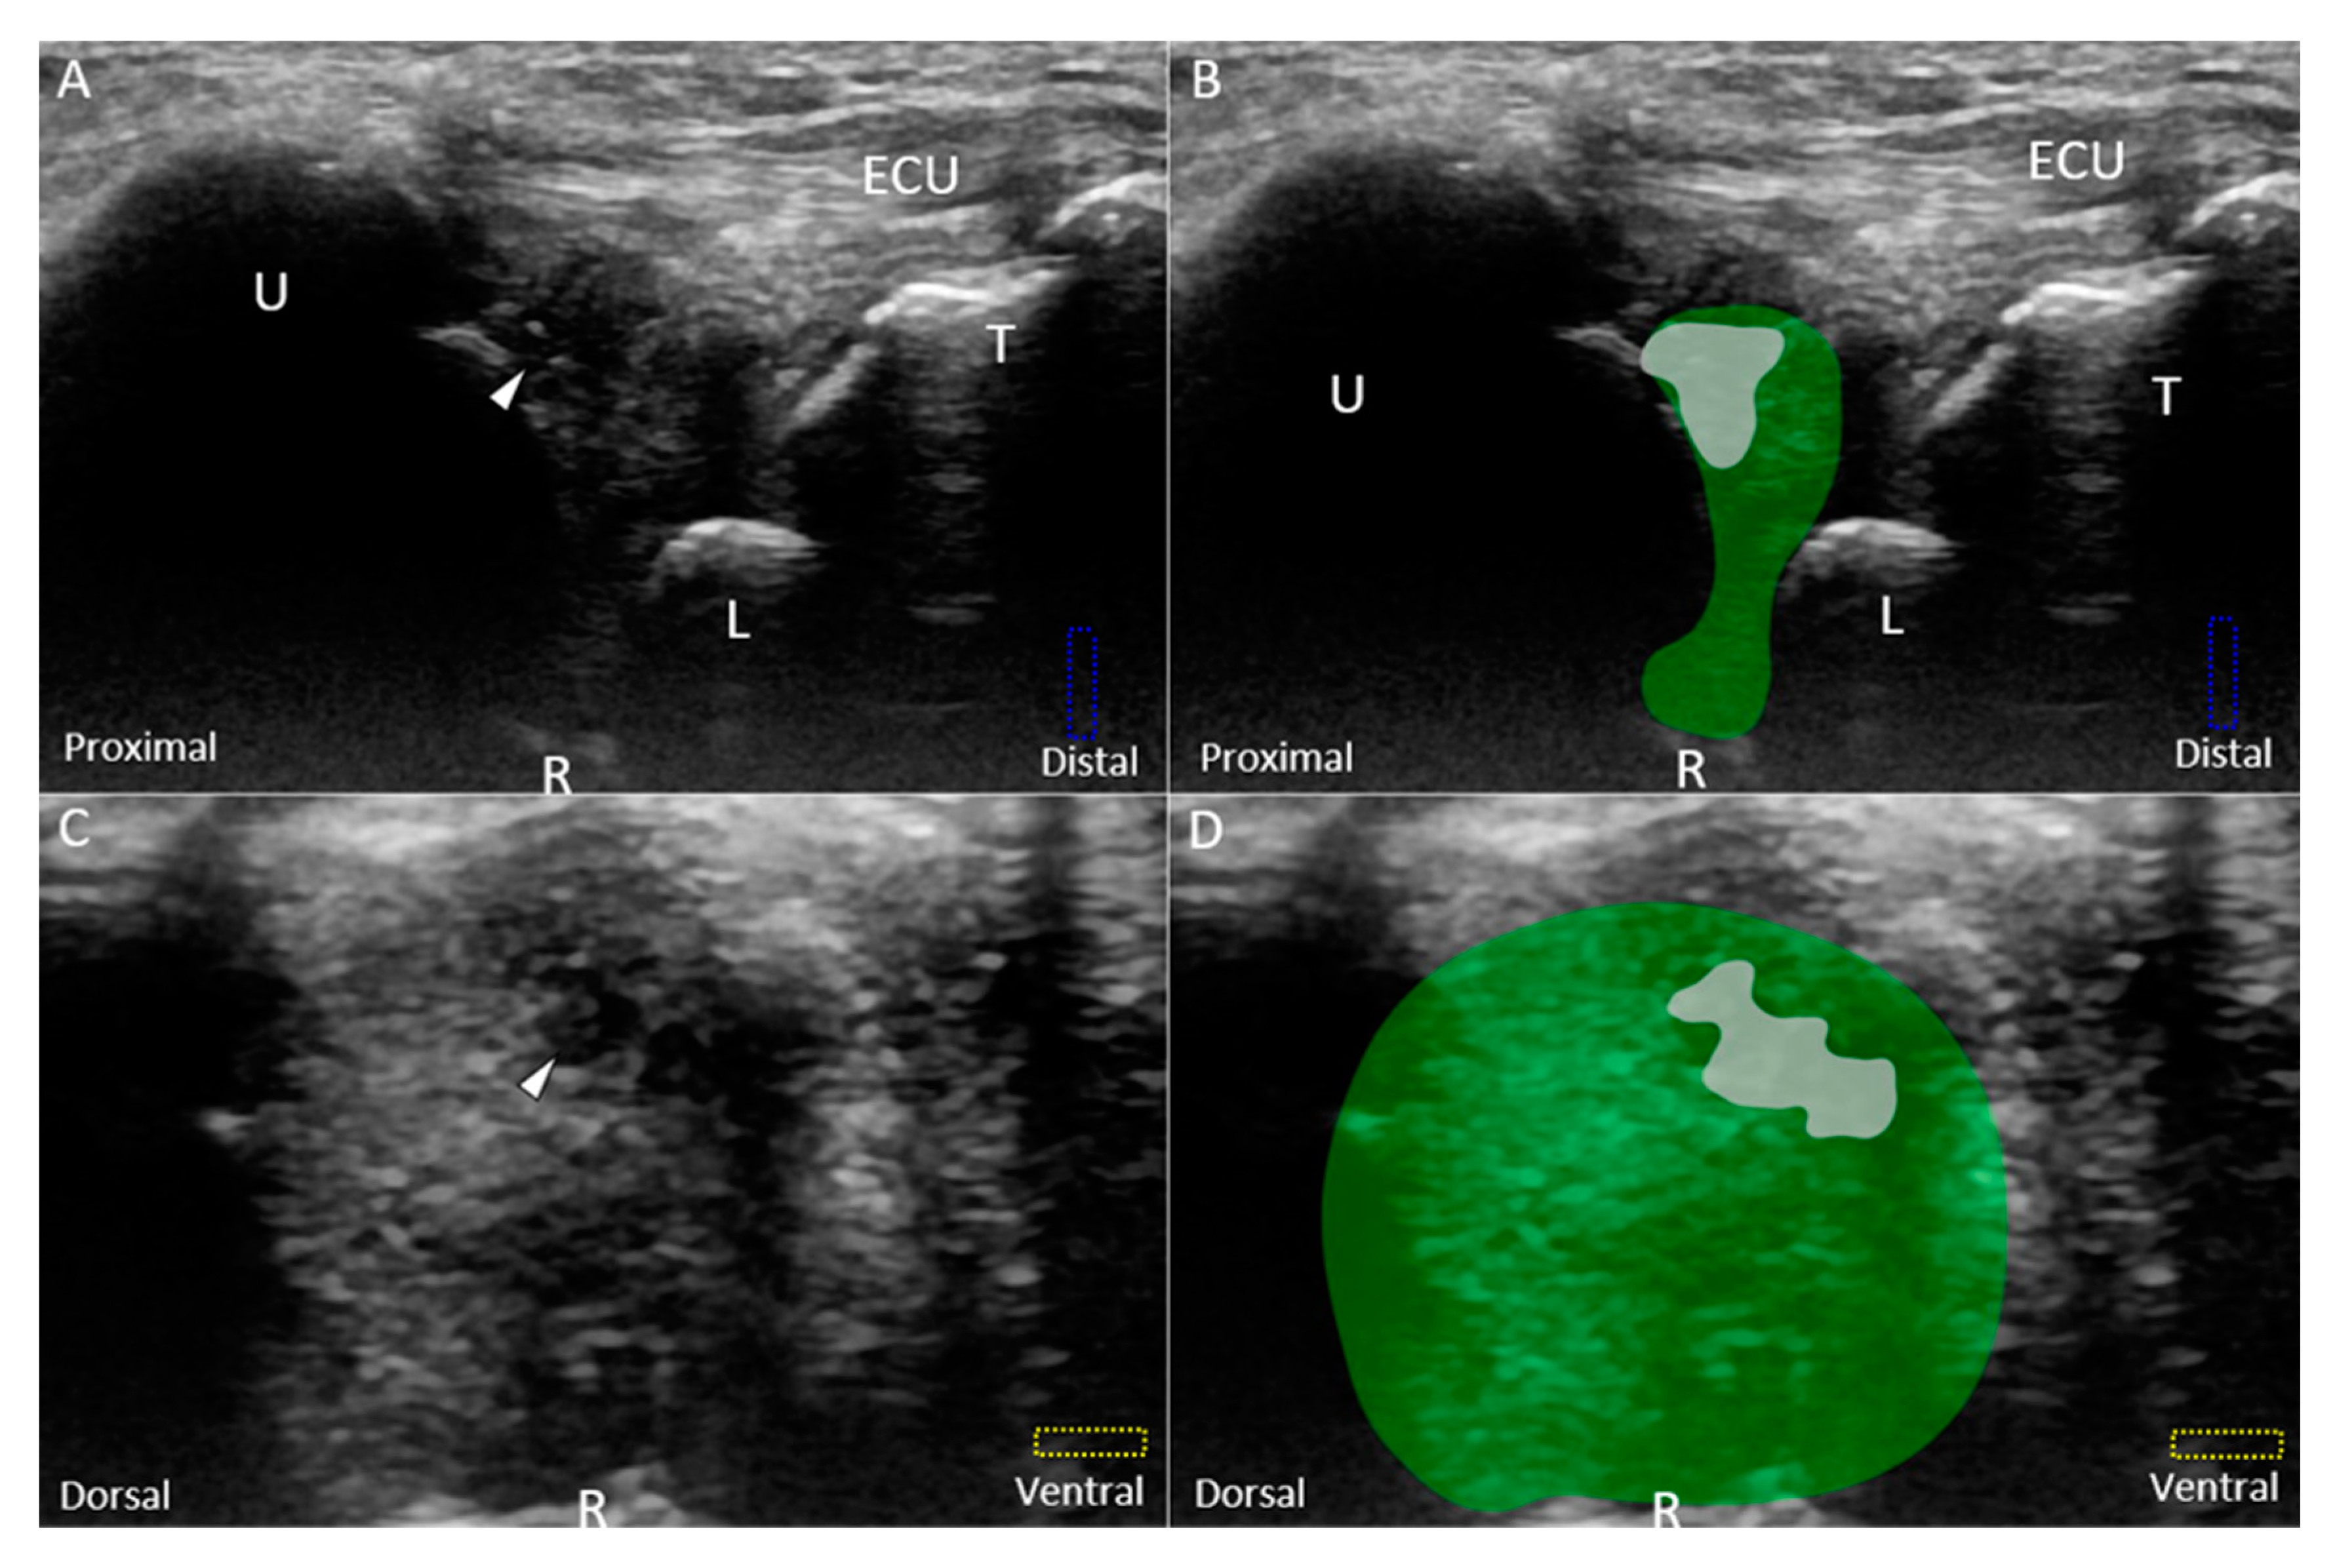

6. US Imaging

6.1. Scanning Protocol

6.1.2. Short-Axis View